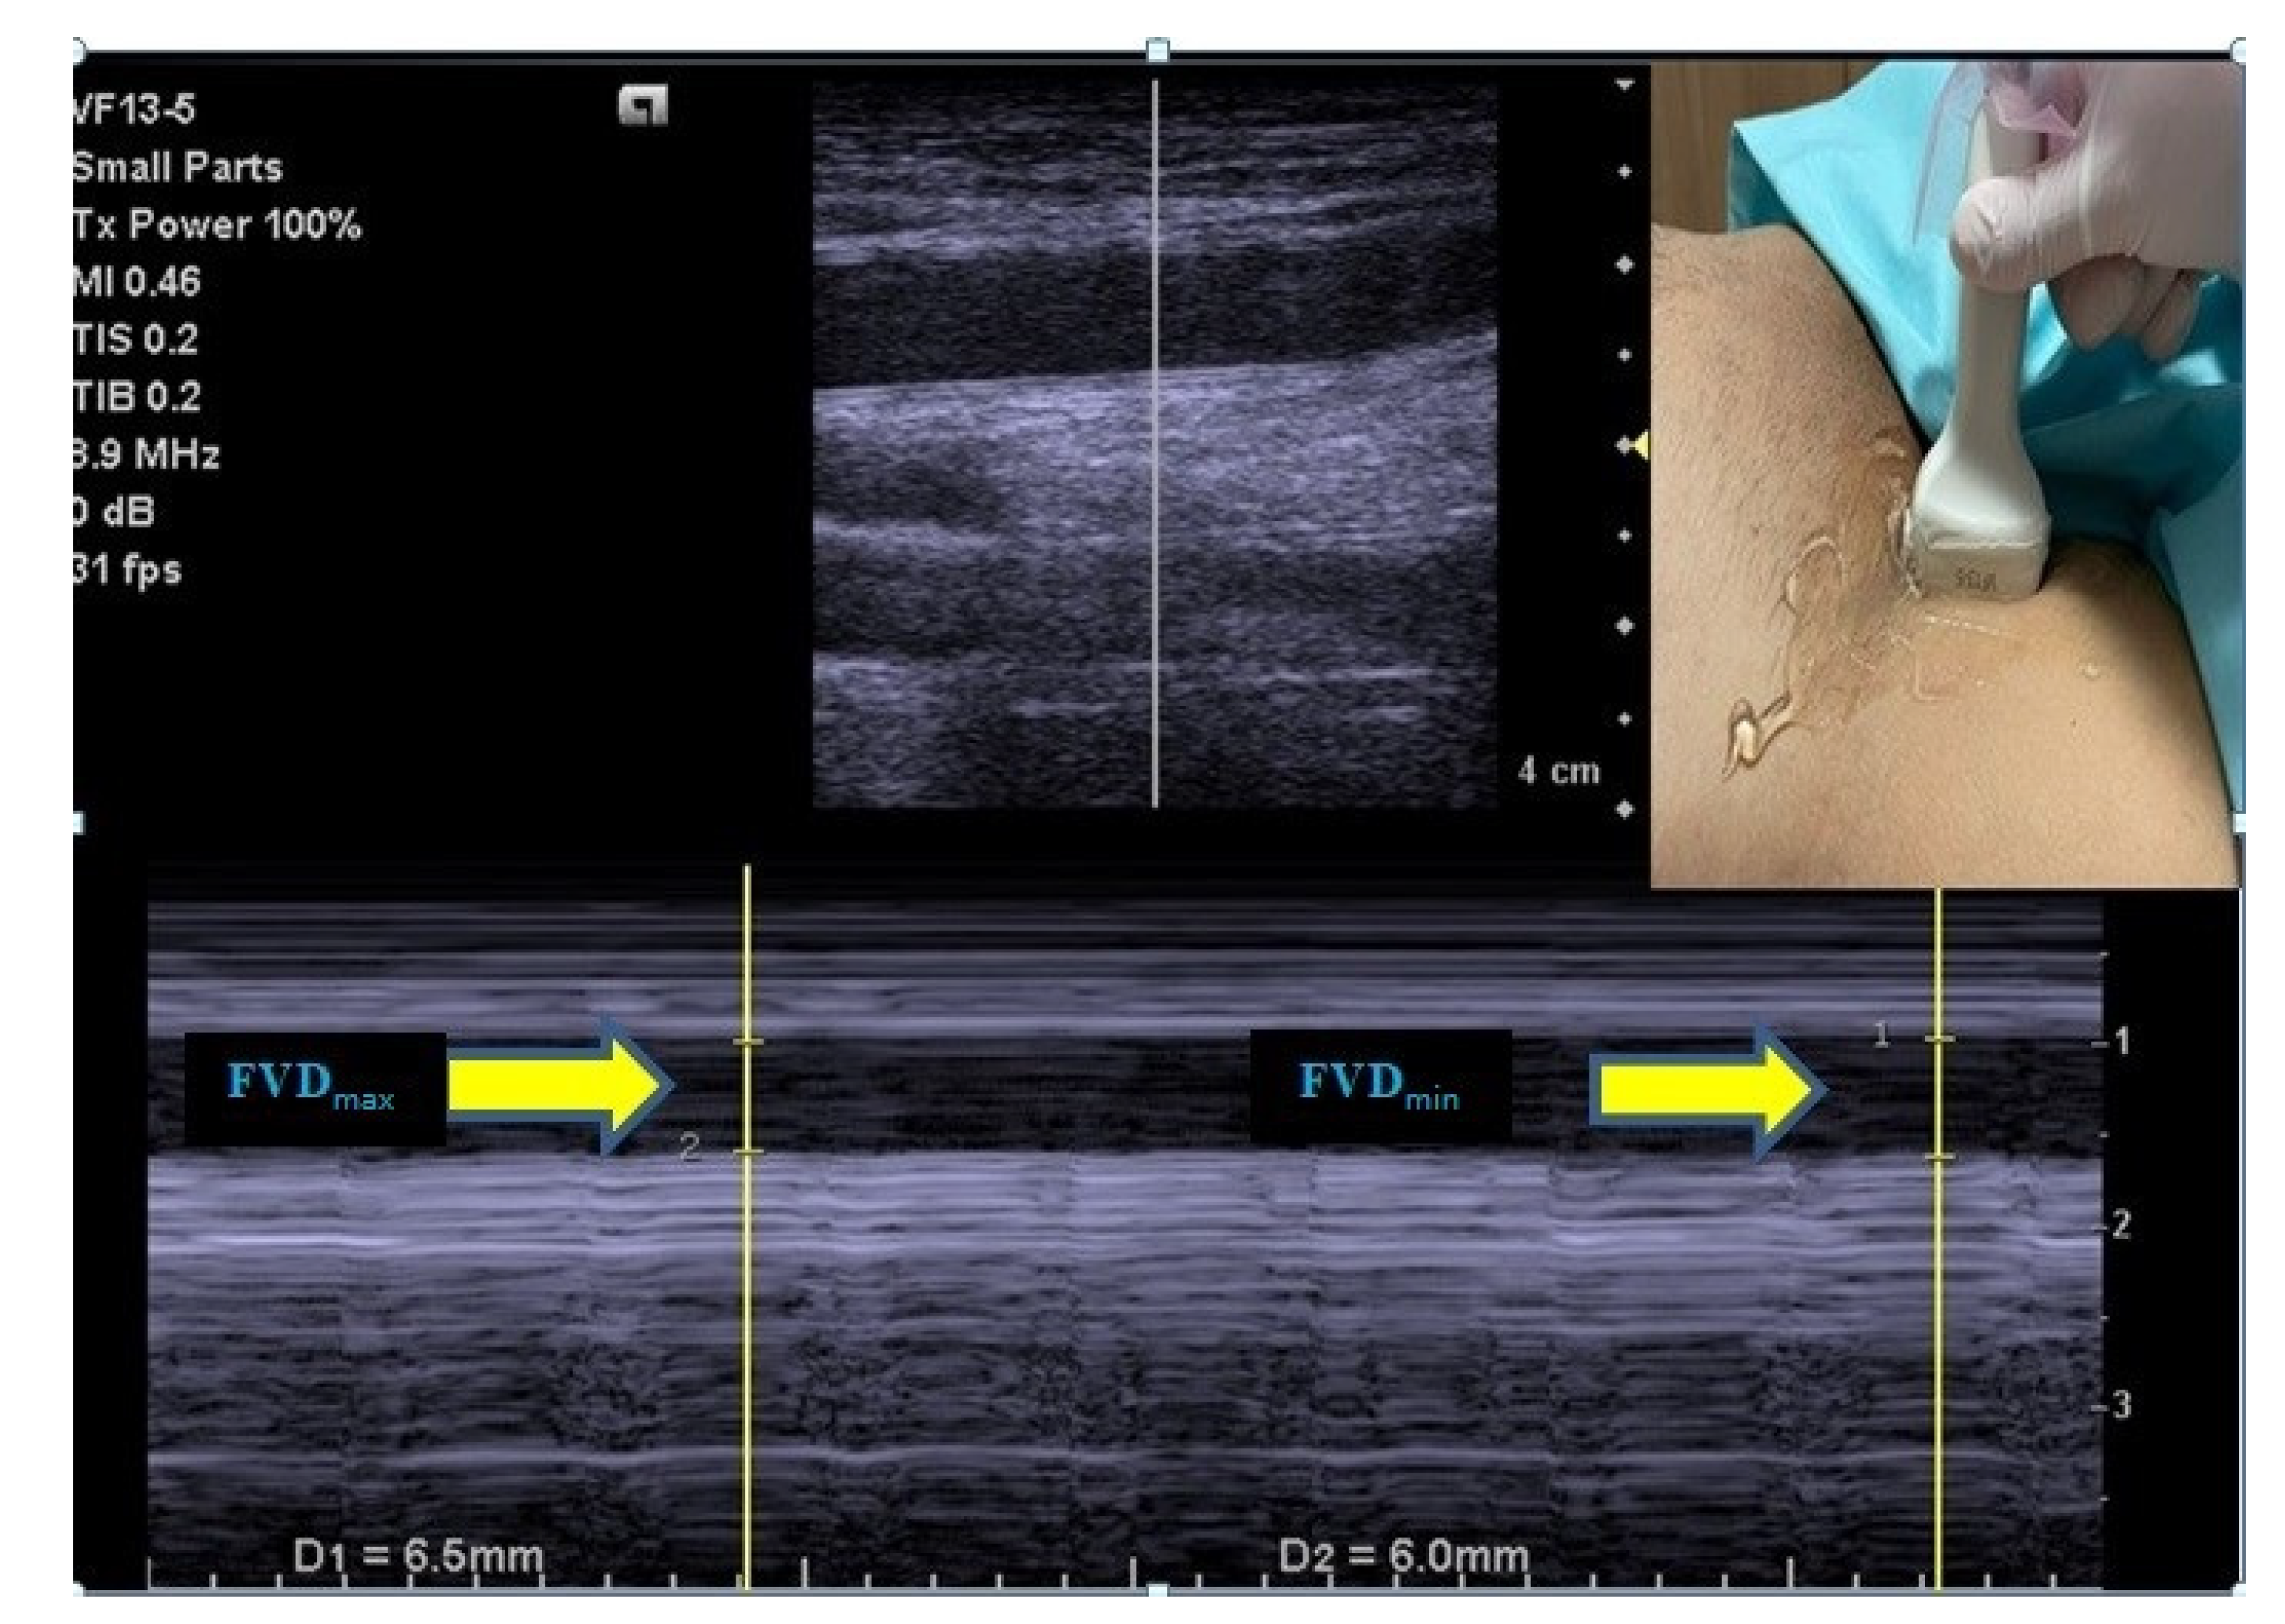

For the purpose of standardization, right femoral vein measurements were used in the study. The FV was visualized with B-mode US, 2–5 cm below the level of the inguinal ligament, just above the inguinal canal, from where the femoral artery was best palpated, without applying any pressure that could affect the diameter of the FV [10]. Next, FV diameter variation during the respiratory cycle [maximum FV diameter (FVDmax), minimum FV diameter (FVDmin)] was measured in the transverse view using a high-frequency linear array transducer [(VF 13–5; 4.1–12.1 MHz), Siemens, USA] on M-mode, and images were saved for reevaluation after the procedure. Using the values obtained, the FV collapsibility index (FV-Ci) was calculated with the following formula: FV-Ci = [(FVDmax–FVDmin)/(FVDmax)] × 100 [10] (Figure 1).

Figure 1. Maximum and minimum diameter measurements of the femoral vein.